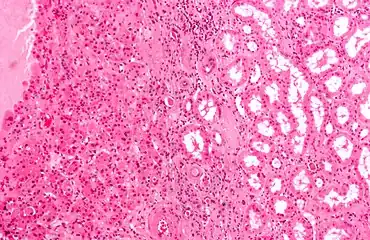

Micrograph of a renal oncocytoma, a type of benign kidney tumour. H&E stain.

On renal ultrasonography, a solid renal mass appears in the US exam with internal echoes, without the well-defined, smooth walls seen in cysts, often with Doppler signal, and is frequently malignant or has a high malignant potential. The most common malignant renal parenchymal tumor is renal cell carcinoma (RCC), which accounts for 86% of the malignancies in the kidney. RCCs are typically isoechoic and peripherally located in the parenchyma, but can be both hypo- and hyper-echoic and are found centrally in medulla or sinus. The lesions can be multifocal and have cystic elements due to necrosis, calcifications and be multifocal (Figure 8 and Figure 9). RCC is associated with von Hippel–Lindau disease, and with tuberous sclerosis, and US has been recommended as a tool for assessment and follow-up of renal masses in these patients.[3]